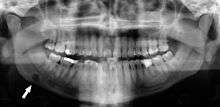

Stafne's defect is usually discovered by chance during routine dental radiography.[4] Radiographically, it is a well-circumscribed, monolocular, round, radiolucent defect, 1–3 cm in size, usually between the inferior alveolar nerve (IAN) and the inferior border of the posterior mandible between the molars and the angle of the jaw. It is one of the few radiolucent lesions that can occur below the IAN. The border is well corticated and it will have no effect on the surrounding structures. Computed tomography (CT) will show a shallow defect through the medial cortex of the mandible with a corticated rim and no soft tissue abnormalities, with the exception of a portion of the submandibular gland. Neoplasms, such as metastatic squamous cell carcinoma to the submandibular lymph nodes or a salivary gland tumour, could create a similar appearance but rarely have such well defined borders and can usually be palpated in the floor of the mouth or submandibular triangle of the neck as a hard mass. CT and clinical exam is typically sufficient to distinguish between this and a Stafne defect. The Stafne defect also tends to not increase in size or change in radiographic appearance over time (hence the term "static bone cyst"), and this can be used to help confirm the diagnosis.[4] Tissue biopsy is not usually indicated, but if carried out, the histopathologic appearance is usually normal salivary gland tissue. Sometimes attempted biopsy of Stafne defects reveals an empty cavity (possibly because the gland was displaced at the time of biopsy), or other contents such as blood vessels, fat, lymphoid or connective tissues. Defects of the anterior lingual mandible may require biopsy for correct diagnosis at this unusual location.[2] The radiolucent defect here may be superimposed on the lower anterior teeth and be mistaken for an odontogenic lesion. Sometimes the defect may interrupt the contour of the lower border of the mandible, and may be palpable. Sialography may be sometimes used to help demonstrate the salivary gland tissue within the bone.